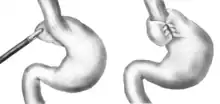

Le traitement chirurgical est la fundoplicature circonférentielle ou partielle. Cette intervention peut se faire par laparoscopie ou laparotomie. Le premier temps opératoire est la correction de la hernie avec repositionnement de la portion herniée de l'estomac dans l'abdomen et redimensionnement de l'orifice hiatal en rapprochant les piliers du diaphragme en arrière de l'œsophage. Le deuxième temps est la création d'une valve antireflux, partielle (type Toupet) ou circonférentielle (type Nissen), ces deux techniques étant d'efficacité équivalente[1].

Des procédures supplémentaires sont parfois effectuées. En cas d'œsophage court, un procédé d'allongement (type Collis) peut être réalisé. Dans certains cas de hernie par roulement, la réparation de l'orifice hiatal est renforcée par une prothèse[1].